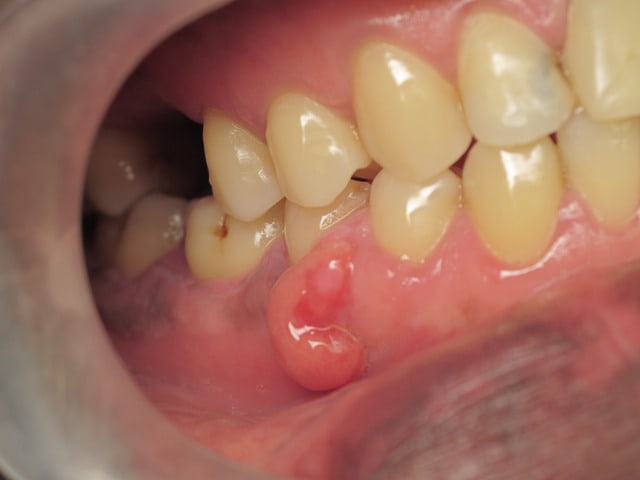

Il présente donc ce pédicule gingival dont le point d'attache semble se situer au niveau de la papille 44 45. D'après l'interrogatoire, il a commencé à apparaître fin juin et ne cesse de grandir. Le patient m'a dit qu'il avait eu la même chose il y a deux ans, qu'une dentiste lui avait retiré sans autre examen. Il n'a pas mal mais souhaitait qu'on lui enlève comme la dernière fois.

Il n'a pas de douleur à la palpation, une légère sensibilité à la percussion sur 44 45. Le test de vitalité est positif sur 45 mais pas sur 44.

Je ne suis pas sûre qu'il s'agisse d'un épulis gingival vu l'aspect de la muqueuse...

tu dois avoir un point d'entrée quelque part et la gencive prolifère en regard de la lésion...

Epulis on le retrouve chez les patientes ( il s'agit d'un patient) au maxillaire supérieur. Donc non...

A couper pour analyse.

Ce nodule est surement a mettre en rapport avec la resorption de la dent.

pas d'accord sur le terme "Epulis" .

Nodule gingival oui